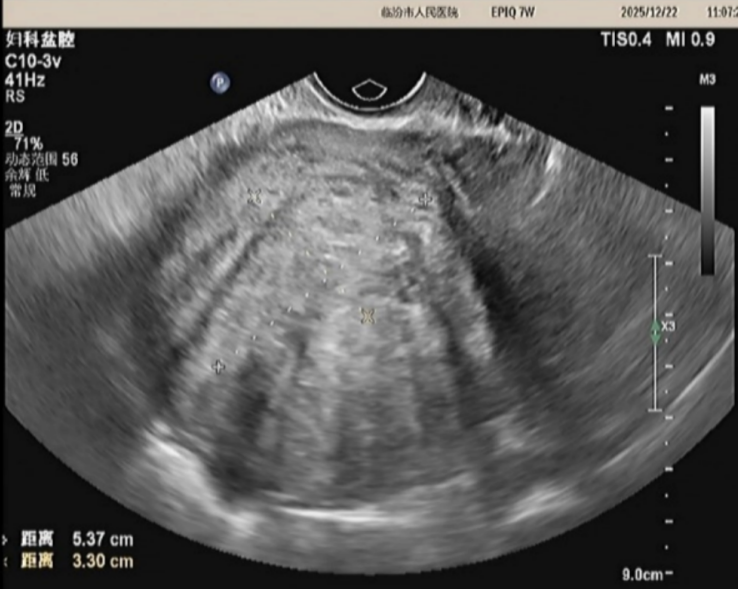

经过术前评估,完善相关检查后,患者于2025年9月25日接受高强度聚焦超声(HIFU)治疗,手术过程顺利,术后无不适,第二天出院。目前术后3个月,正常行经2次,痛经症状明显好转,经量减少,通过术前术后的超声影像学的对比,患者子宫腺肌瘤瘤体的大小及子宫的大小较前明显缩小,瘤体的大小由术前的6.6*6.6cm缩小为5.3*3.3cm,子宫的大小由术前的10*9cm缩小为8*7cm。预计随着时间的时间的推移,治疗效果将更加明显。

治疗三个月后